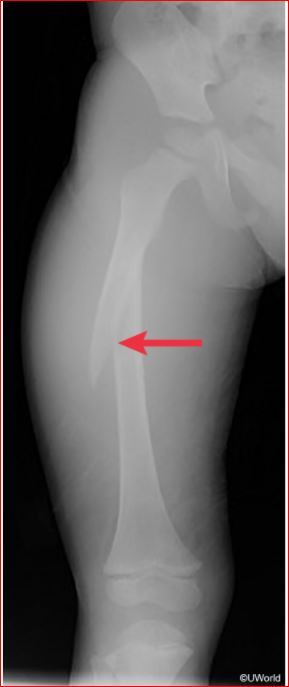

A femur fracture in a nonambulating child

A femur fracture in a nonambulating child, particularly a spiral fracture, is suspicious for a twisting force on the thigh.

WARNING SIGNS OF CHILD ABUSE

Red flags for child abuse include?

Posterior rib fractures,

metaphyseal corner fracture (“bucket-handle”) and

fractures at various stages of healing.